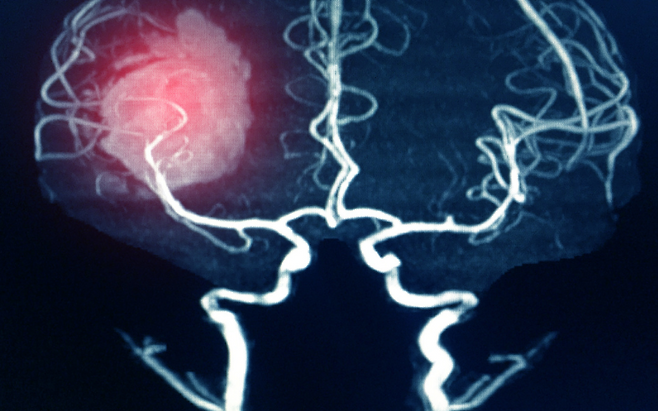

뇌출혈은 예고 없이 찾아오고, 한 번 겪으면 삶 전체를 송두리째 흔든다. 단 한 번의 출혈로 말이 어눌해지거나, 반신마비가 오기도 하고, 심할 경우 목숨까지 잃을 수 있다.

뇌출혈의 가장 큰 원인은 고혈압이다. 높은 혈압은 뇌혈관을 약하게 만들고, 결국 작은 충격에도 혈관이 터지게 한다. 혈압은 숫자가 아니라 생명줄이다. 하루 10분 걷기, 싱겁게 먹기, 충분한 수면, 스트레스 관리.

이 네 가지를 꾸준히만 해도 혈압은 안정된다. 특히 아침에 일어나기 전, 갑작스럽게 움직이기보다 몸을 천천히 일으키는 습관도 중요하다. 혈압이 급상승하는 순간이 뇌출혈 위험의 시간대다.